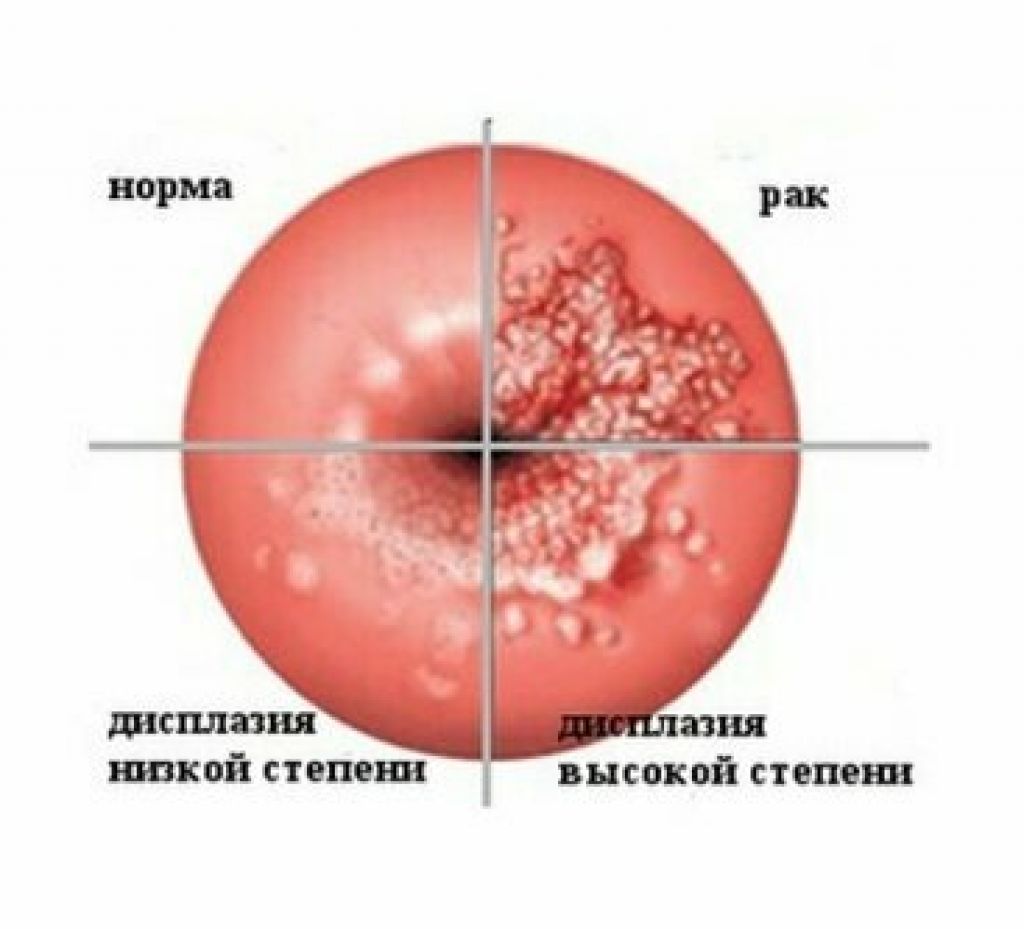

Симптомы кондилом могут варьироваться, и визуальное представление этого заболевания может быть различным. Некоторые кондиломы выглядят как небольшие бугорки или бородавки, в то время как другие могут иметь форму плоских пятен или цветных наростов.

Для профилактики кондилом важно соблюдать безопасные половые отношения, использовать презервативы и регулярно проходить медицинские осмотры. Раннее обнаружение и лечение кондилом помогут предотвратить распространение инфекции и снизить риск возникновения осложнений.